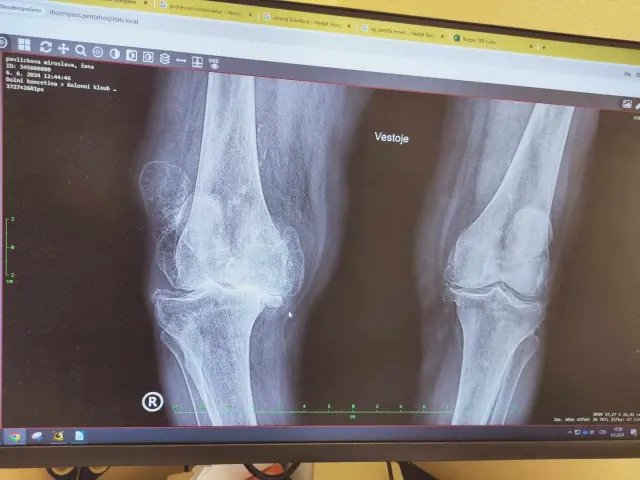

Pomoc bude směřovat na zajištění mobility více než 90leté babičky, která se po těžkém úraze a neúspěšné léčbě, v kombinaci s velmi vysokým stářím stala již zcela imobilní. V reálu je její koleno 2,5× větší než druhé (RTG snímek nezachytí) stav je už nezvratitelný, doživotní.